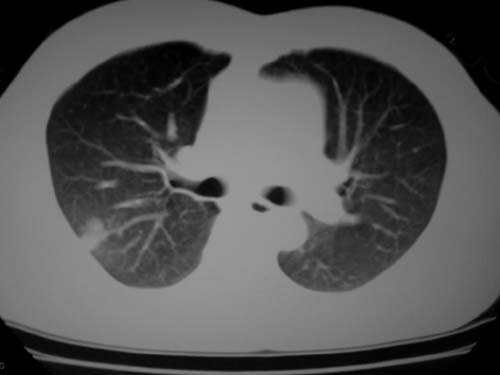

标题: CT19540: 31岁。自述结核性胸水治疗两个月后,在外院拍x线发 [打印本页]

标题: CT19540: 31岁。自述结核性胸水治疗两个月后,在外院拍x线发

右侧胸壁结节状软组织影伴相应肺叶内受侵,伴右侧胸腔积液。考虑:结核性可能大。

支持 右侧胸壁结节状软组织影伴相应肺叶内受侵,伴右侧胸腔积液。考虑:结核性可能大。

右侧胸壁结节状软组织影伴相应肺叶内受侵,伴右侧胸腔积液,结合临床,首先考虑结核。

考虑结核性胸膜炎,胸膜肥厚,不除外胸膜间皮瘤可能,建议复查。

1)考虑右侧结核性胸膜结节。2)右侧胸膜增厚+包裹性胸腔积液。